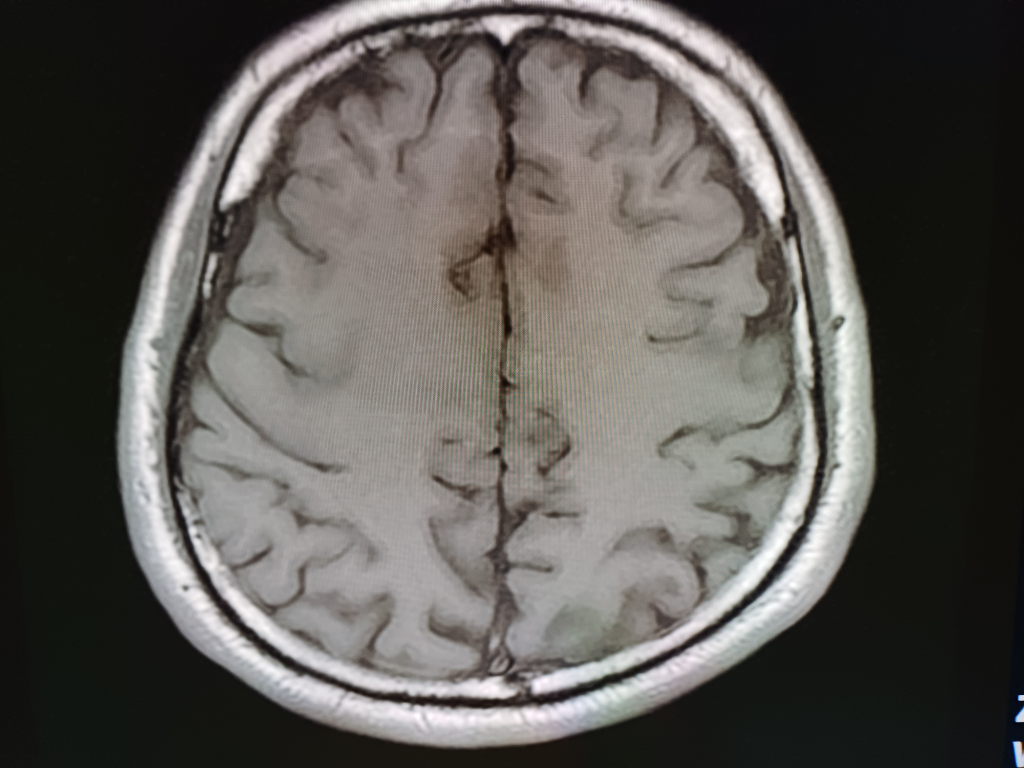

뇌 mri mra를 찍었는데 전문가분들의 고견을 구합니다.

안녕하세요.불편한 어지러움이 한달이상 지속되어 혹뇌쪽 이상이 아닌가 싶어 오늘급하게 mri mra를 촬영하고 왔습니다.결과를 바로 확인할수 있는줄 알았으나 일주일정도 기다려야 판독이 나온다하여 급한 마음에 사진 몇장 첨부하오니 답변해주시면 감사하겠습니다!!

• 1번 째 사진

업로드해주신 MRI 및 MRA 영상은 특별히 이상한 소견이 보이지 않습니다

뇌실질에 이상소견 없으며 뇌혈관이 막여있거나 좁아진 부분도 보이지 않습니다

현재 올려주신 사진만으로는 아주 큰 병변 이 있어 보이지는 않으나, MRI의 경우 연속된 단면을 모두 봐야 병변을 정확히 확인할 수 있으므로 해당 사진들만으로는 병변의 유무를 모두 다 확인 불가능합니다. 추후 판독을 기다려 보시기 바랍니다.